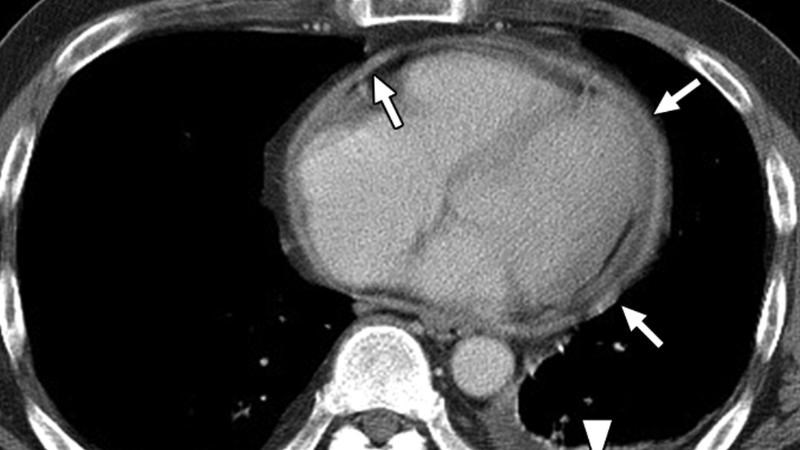

- Chụp cắt lớp vi tính (CT - scan) lồng ngực: Kết quả xét nghiệm này giúp bác sĩ nhìn thấy rõ nét hơn tình trạng của tim, hỗ trợ chẩn đoán phân biệt với các triệu chứng khác có thể gây đau ngực ở người bệnh.

CT-scan lồng ngực được dùng để chẩn đoán viêm màng ngoài tim